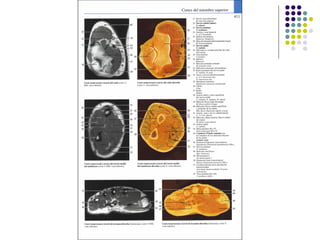

La extremidad superior humana incluye el hombro, el brazo, el codo, la muñeca y la mano. Está diseñada para una variedad de funciones motoras finas como agarrar objetos y realizar tareas manuales complejas. La coordinación precisa de los músculos y los huesos de la extremidad superior es clave para su versatilidad funcional.